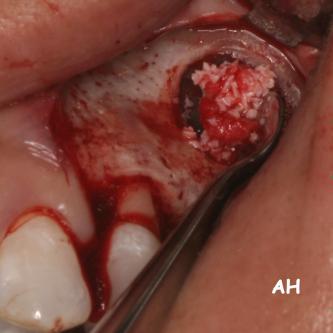

Exemple 11: Pendant l'implantation on remarque un manque d'os sur la partie externe, les spires de l'implant sont visibles.

Exemple 11: Une greffe d'os est effectuée afin de compenser l'épaisseur d'os manquante.